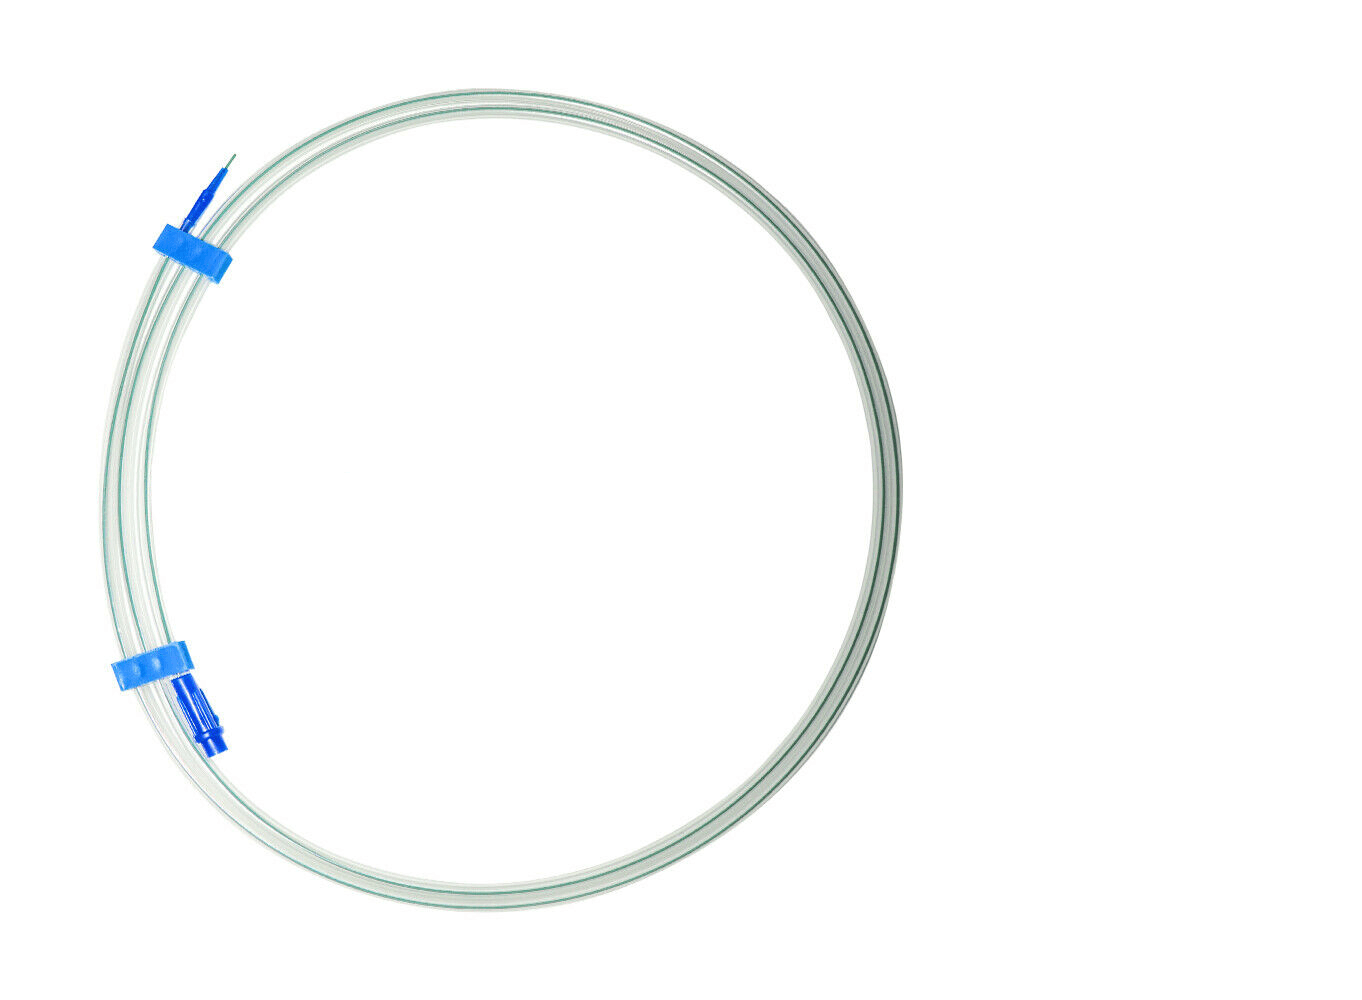

PTFE Guide Wire Set of 10 Urology Size 0.035 Length 150cm Straight

PTFE Guide Wire Set of 10 Urology Size 0.035 Length 150cm Straight

Guide wire with and without PTFE coating

- This wire is made by Galvanized Stainless Steel, and having fixed core. UROMED guide wire has excellent flexibility.

- Better push ability for increased placement control.

- Low of coefficient of friction for smooth advancement.

- Size: 0.035”

- Lengths: 150cm

Images are for illustration only. Company may change item design and packaging from time to time. We will ship latest stock available.